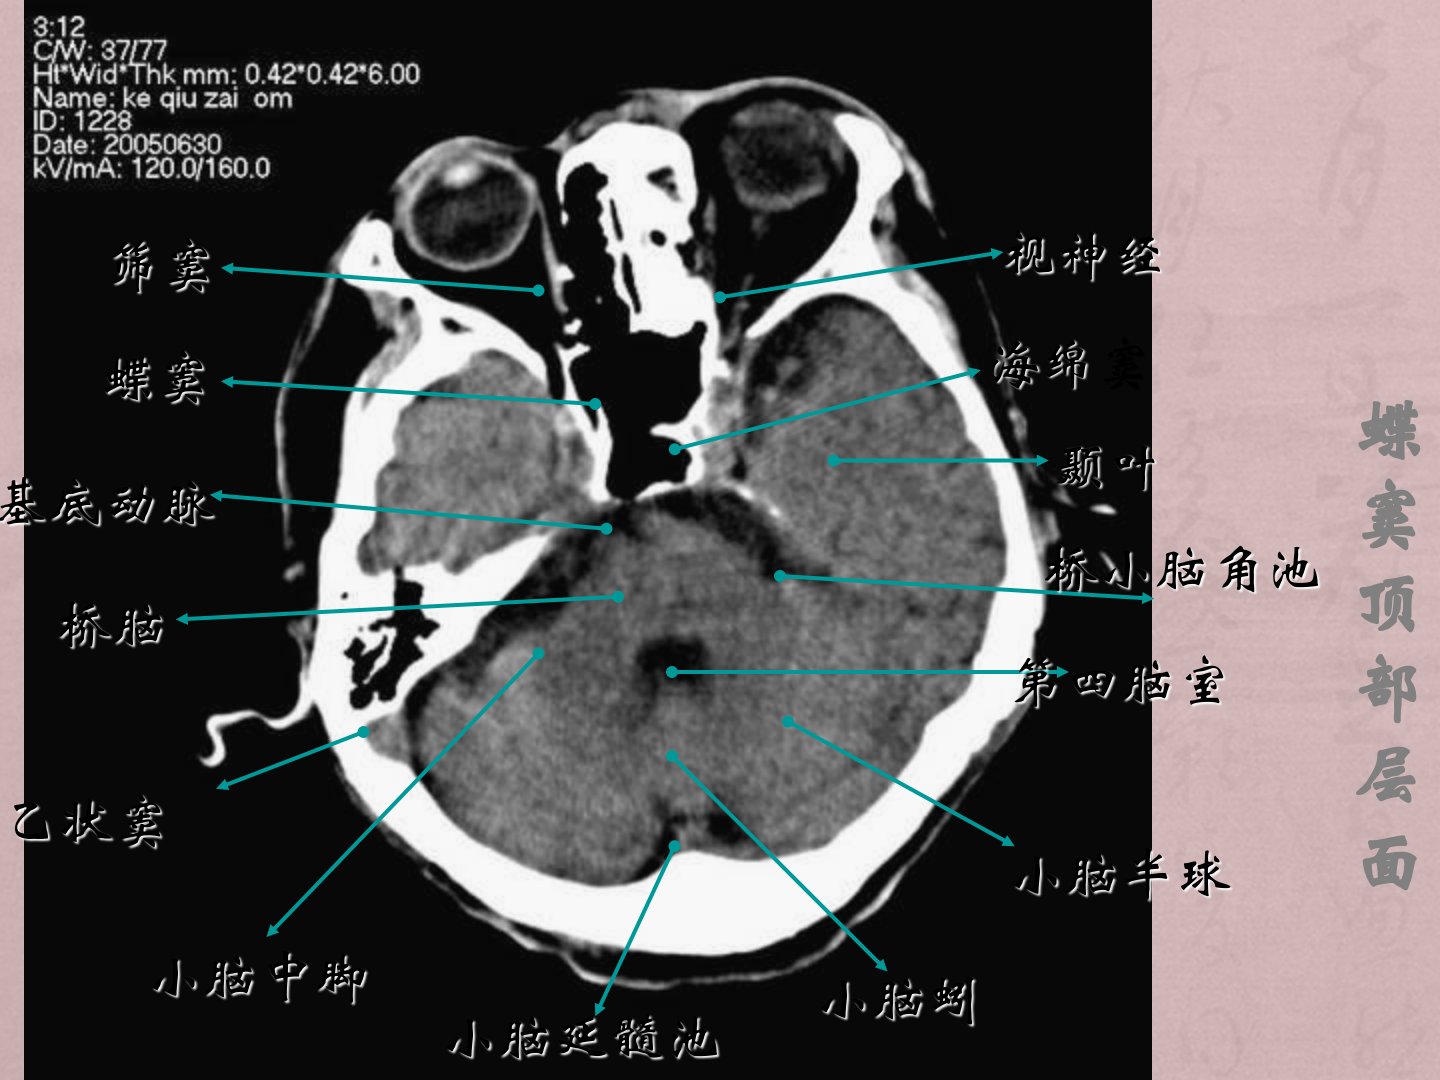

一颅脑基本解剖二常见疾病(1)脑血管病(2)颅脑外伤(3)颅内肿瘤性病变(4)颅内感染性病变、蝶窦顶部层面筛窦桥脑小脑中脚小脑蚓小脑半球第四脑室海绵窦颞叶桥小脑角池蝶窦乙状窦基底动脉视神经小脑延髓池鞍上池层面中脑大脑脚外侧裂池额叶直回四叠体池海马环池枕叶脚间池颞叶侧脑室下角小脑蚓下丘第三脑室下部层面额叶纵隔裂侧脑室前角第三脑室上丘四叠体池松果体(钙化)外侧裂池枕叶丘脑岛叶侧脑室后角尾状核头第三脑室上部层面大脑镰额叶胼胝体膝部尾状核头部侧脑室前角透明隔穹窿部丘脑室间孔中间帆池脉络丛外侧裂池枕叶侧脑室三角区视辐射内囊前肢内囊后肢侧脑室体部层面颞叶侧脑室体部放射冠额叶胼胝体压部上矢状窦枕叶胼胝体膝部...